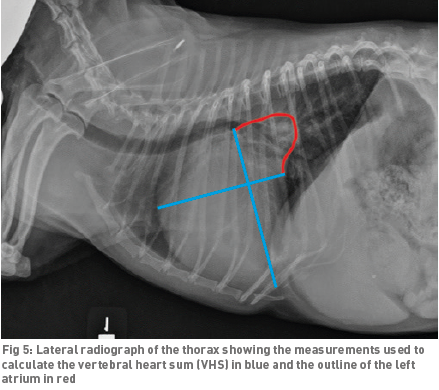

• VHS measurements to detect enlargement

The Vertebral Heart

Size or Scale or Sum (VHS) is an objective means of measuring

heart size.

As

the x-ray image above shows, using calipers, they

measure the length (from the apex to the bottom of the left mainstem) and width

(at

its widest point perpendicular to the lemgth measurement) of the heart

on a lateral x-ray and compare those dimensions

to the number of veterbrae from T4 to T12, to calculate the VHS value. Since

the dog's own vertebrae are used for comparison, each VHS value is

normalized to the dog's overall body size.

See

this

YouTube video for details. A diagram showing how the VHS is calculated

is

here. This is called the Buchanan VHS method, devised

by Dr. James W.

Buchanan, a pioneer in the research of MVD in cavaliers, in

1995. See his

1995 article.

The VHS is not intended to diagnose CHF. It's purpose is to enable veterinarians to more accurately determine enlargement of the heart (called cardiomegaly or dilation) and the progression at which the enlargement is occurring, which usually is due to MVD. However, since MVD normally initially causes only the left atrium (LA) to enlarge, the VHS method is not precise enough to measure only the size of the LA. See for example, the x-ray at left, which shows that the VHS measurements entirely miss the bulbous enlarged LA in the upper right corner of the heart. (Image from Hezzell, 2018.)